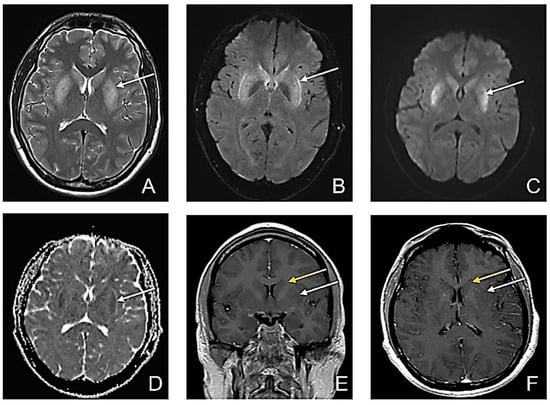

| Disease | T1w Sequence | T2w Sequence | FLAIR | DWI |

|---|---|---|---|---|

| Hypoxic-ischemic encephalopathy [13,14] | In severe cases, hyperintensities may be encountered due to the accumulation of denatured proteins, secondary to necrosis | In the first two weeks, hyperintensities and swelling of the affected areas due to inflammation of the affected grey matter can be observed | Hyperintensities in the affected areas | Increased DWI signal and low ADC, suggestive of restricted diffusion |

| Leigh disease [15,16] | Decreased T1wi signal in the areas with T2 hyperintensities; rarely, T1 hyperintensities may be encountered | Hyperintensities in the following structures: basal ganglia (especially putamen), brain stem, periaqueductal brain matter, medulla, midbrain, thalami | Hyperintensities such as T2wi | Restricted diffusion may be seen in the acute setting |

| Hypoglycemic encephalopathy [17,18,19] | Hyposignal (usually bilateral) in the cerebral cortex, internal capsule, hippocampus, or basal ganglia | Hyperintensity in one or more of the T1w-mentioned structures | Hyperintensities such as T2wi | It is a sensitive sequence showing reversible diffusion restriction from the early hours |

| Wilson’s disease [20,21] | Hypointensities in deep grey matter structures | Hyperintensities in deep grey matter structures, especially in the putamen and bilateral thalami. Giant panda sign (increased signal intensity in the midbrain tegmentum with the normally hypointense red nucleus | Giant panda sign. | Restricted diffusion may be the first imaging change |

| Toxic substances [22,23] | It depends on the substance involved | Generally, T2 hyperintensities in the affected areas | Generally, FLAIR hyperintensities in the affected areas Confluent, symmetrical lesions that may involve the corpus callosum | Confluent and symmetrical restricted-diffusion lesions that may involve the corpus callosum or white matter |

| Hepatic encephalopathy [24,25] | Hyperintensities in the basal ganglia, subthalamic regions, and globus pallidus | High signal intensities involving the hemispheric corticospinal tract and focal hyperintense T2 lesions in subcortical hemispheric white matter | Hyperintensities such as T2wi | Increase mean diffusivity in the affected areas |

| Non-ketonic hyperglycemia [26,27] | Hyperintensities in the basal ganglia (more often, the putamen or caudate nucleus are involved) | Hyperintensities in the regions described in the T1w sequence | Sometimes subcortical hypointensity and cortical hyper signal | Basal ganglia hyperintensity |